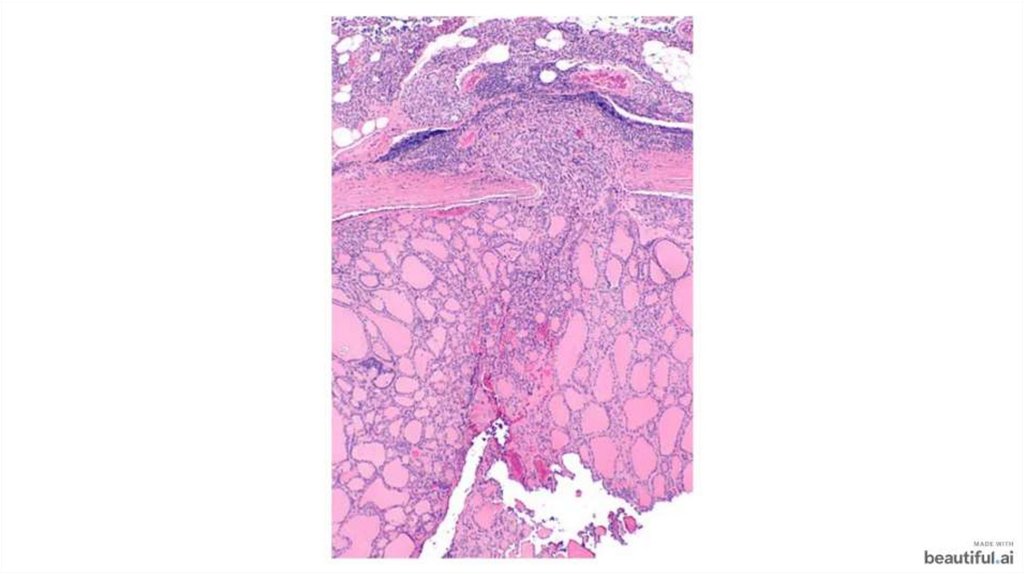

Фолликулярный и папиллярный рак щитовидной железы